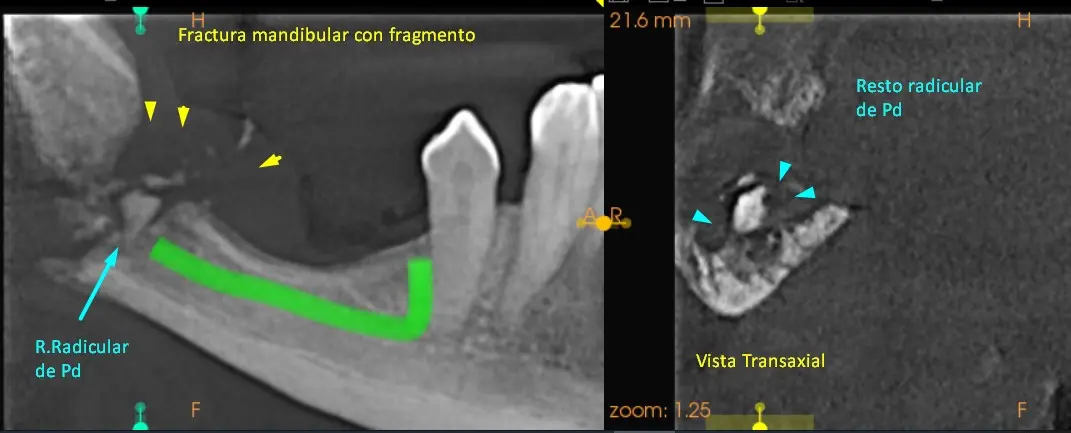

Para mayor información detallada se procedió a realizar una tomografía Cone Beam que abarque mas la zona de interés: zona Rama y Angulo de la mandíbula. Ver imágenes 6 a imagen 9.

Tanto en la radiografía panorámica (imagen 1) como la tomografía maxilar inferior se puede observar una fractura mandibular a la altura del Angulo de la mandíbula con resto de fragmento óseo. (Fx Conminutas) Como también se logra ver todavía resto radicular de pieza dentaria. Ver imágenes 2 a imagen 5.